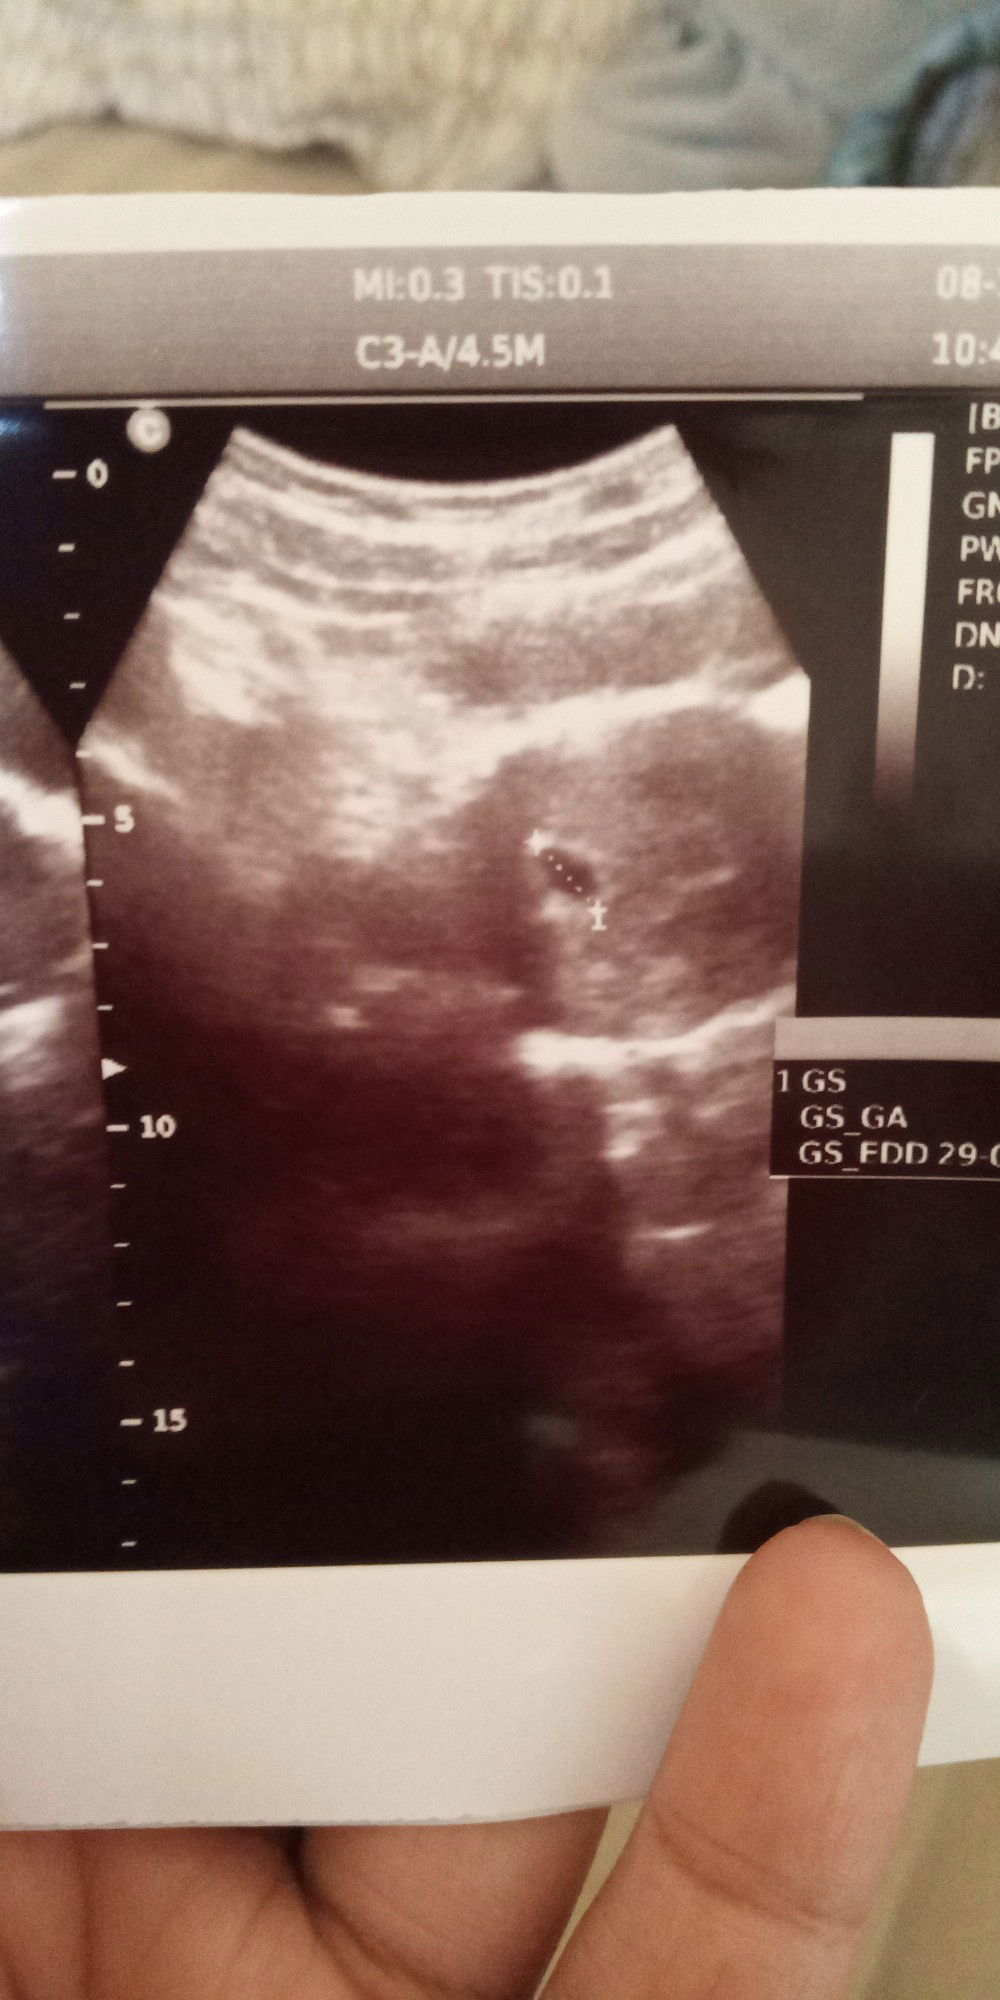

Bunda tanya dong Alhamdulillah udah 6week Tapi kok keluar darah kayak mens ya bunda Tapi kondisi semua normal Bahaya nggak bunda yaa